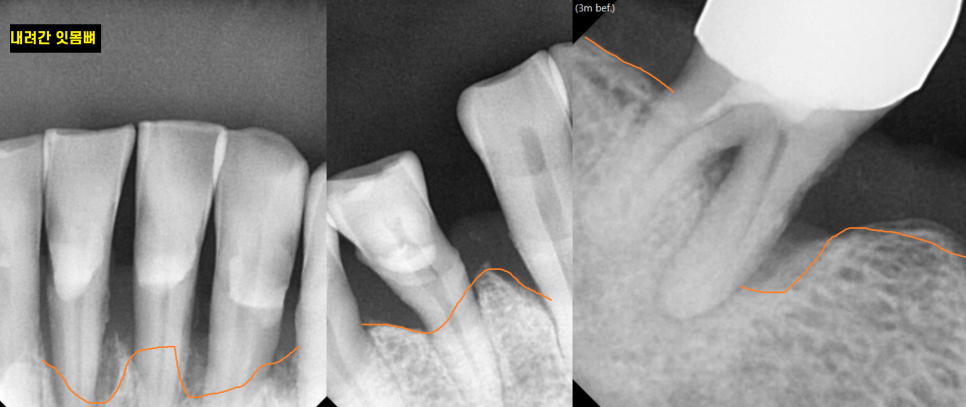

X-RAY를 촬영해보았을 때

전형적인 풍치 증상이네요~

잇몸뼈가 빨간색 라인까지

치아 머리 부분까지

채워져있어야하지만

환자분은 주황색 부분까지 내려간 상황이었습니다.